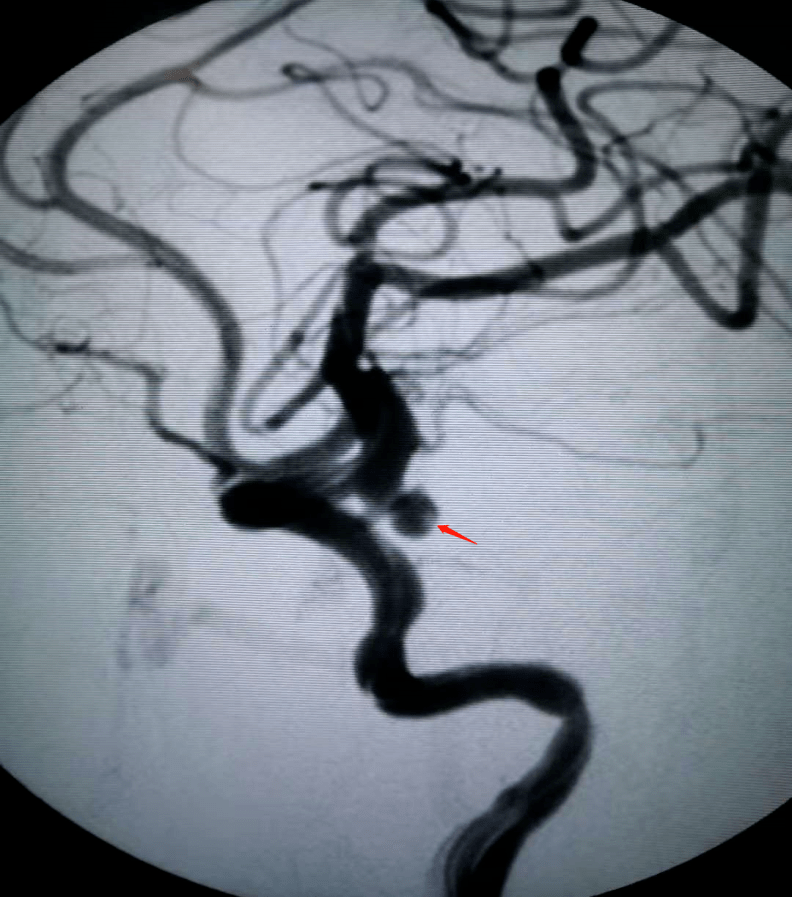

急诊行脑血管造影术 动脉瘤栓塞术治疗头颅mra:左侧颈内动脉c7段动脉

图片尺寸792x897